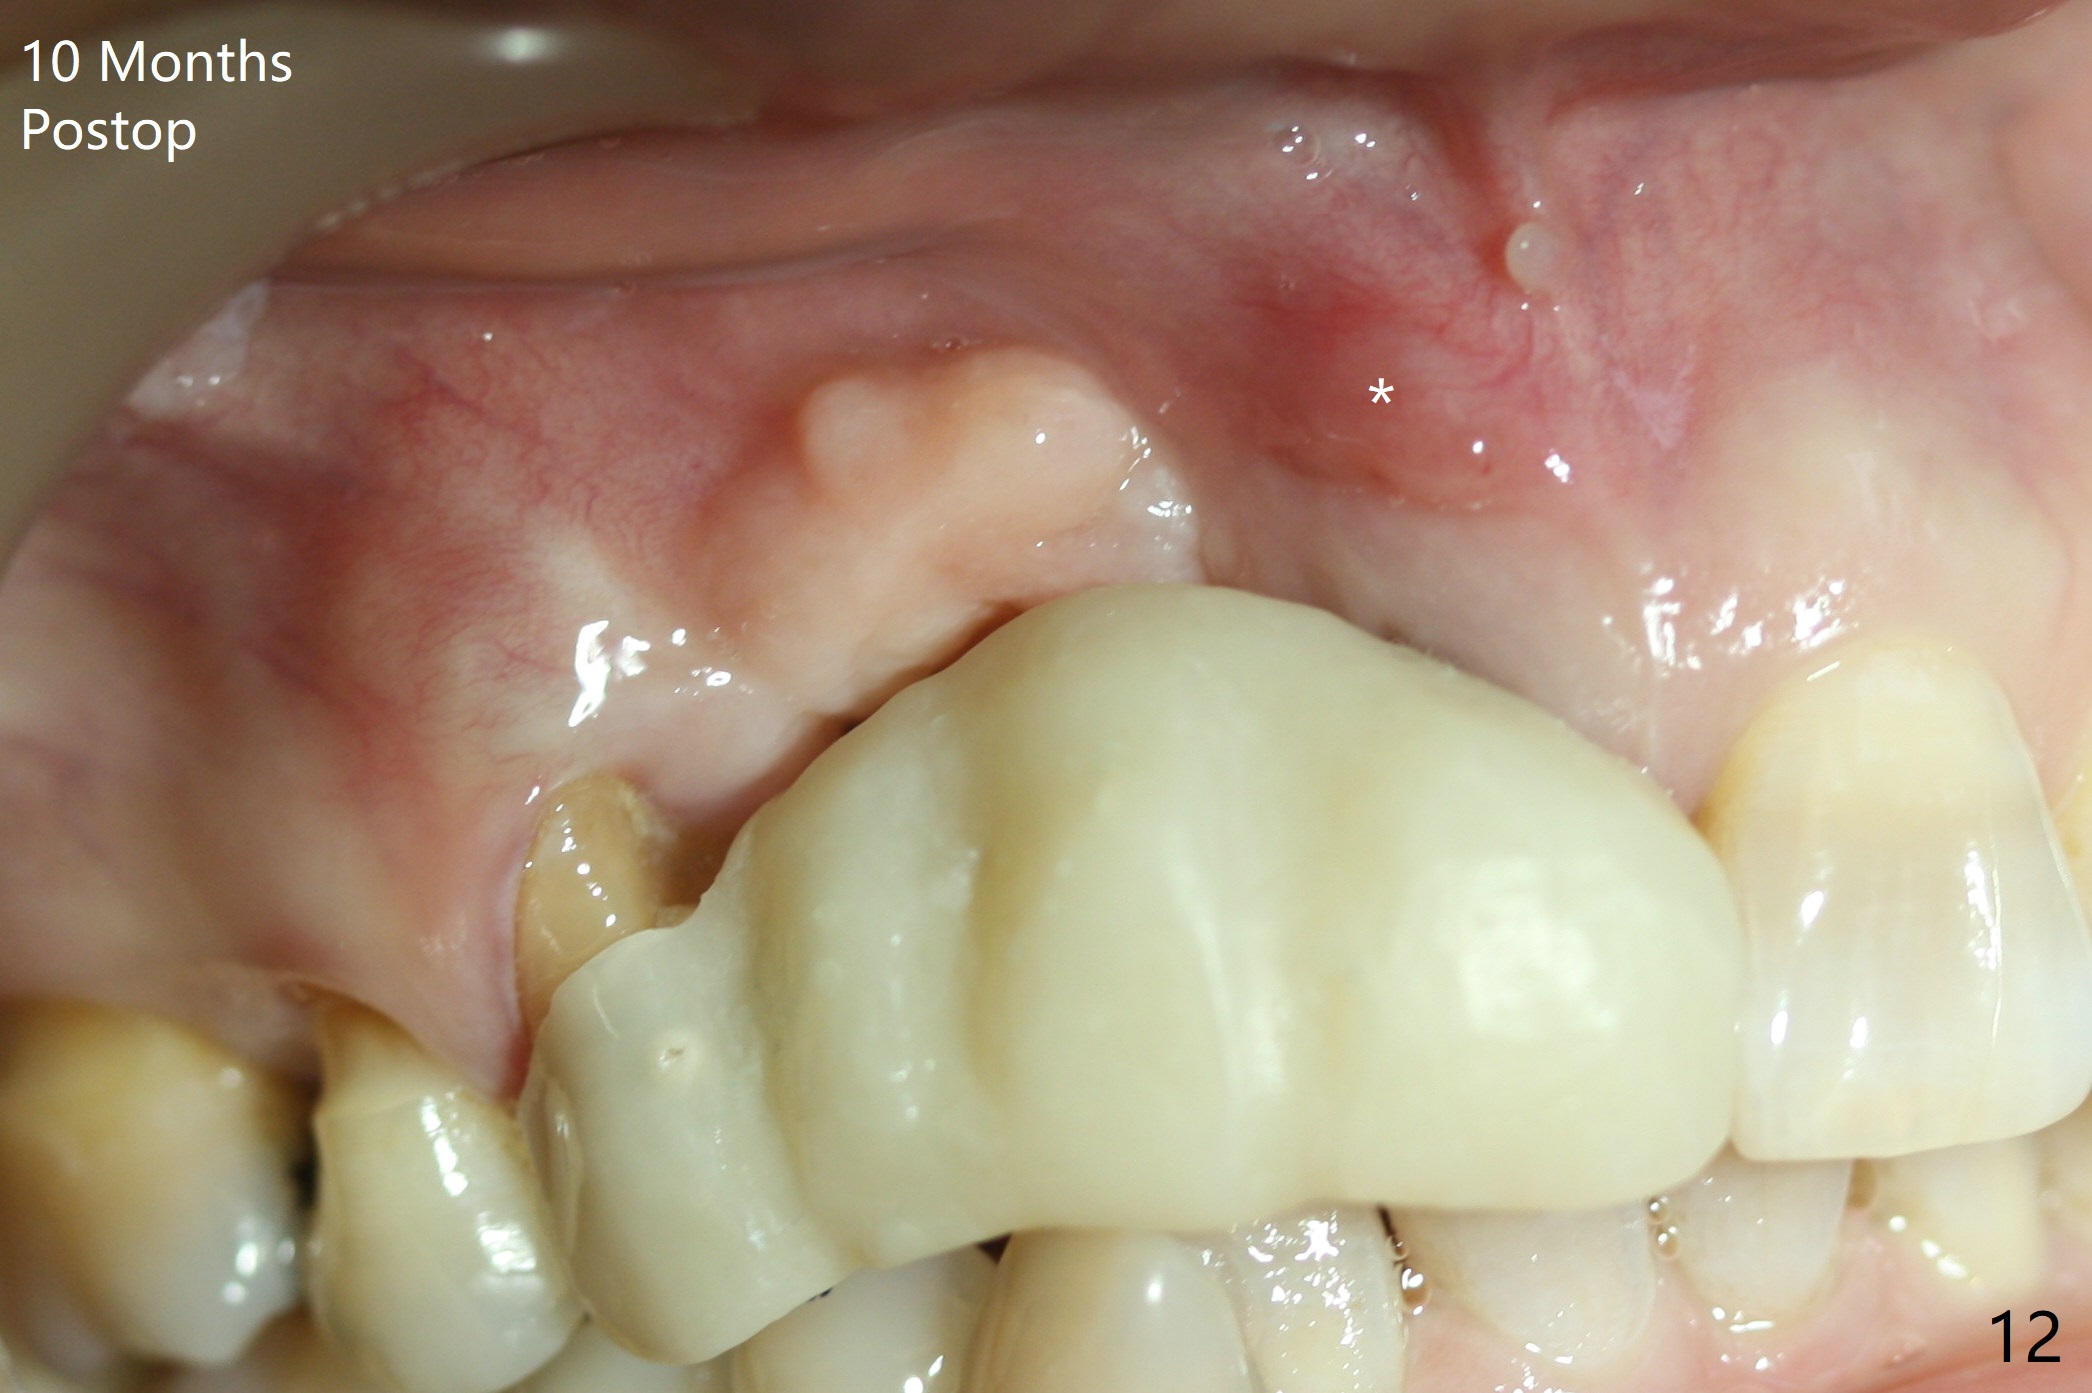

An asymptomatic erythema develops at #8 10 months postop (Fig.12 *). A fistula forms 11 months postop (Fig.13 < ) and is associated with implant thread exposure (Fig. 14 >, as compared to Fig.2). It appears that bone graft and possible block graft are needed with PRF after debridement with Titanium brush.